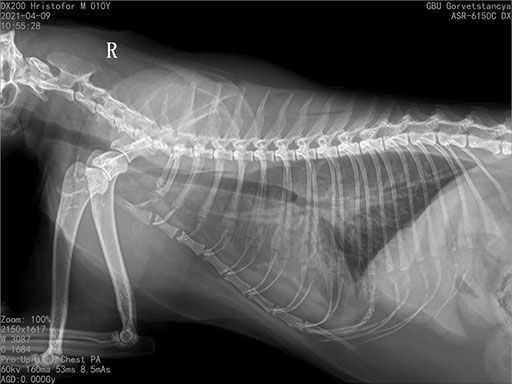

Коллиматорный прицел формирует пучок рентгеновского излучения на участок исследования. Проходя через ткани тела, излучение попадает на плоскопанельный цифровой детектор, который, в свою очередь, передает сигналы на компьютер.

В считанные секунды полученные данные обрабатываются компьютером посредством установленной на него программы визуализации, и сформированное клиническое изображение выводится на монитор лаборанта.

Клинические изображения (снимки) можно напечатать на принтере, сохранить в архиве или отправить по сети коллегам для оперативного консилиума.

Цифровая рентгеновская установка ASR-6150C поставляется с мобильным столом пациента и комплектом рентгенопрозрачных анатомических ложементов всех размеров, видов и пород домашних животных.